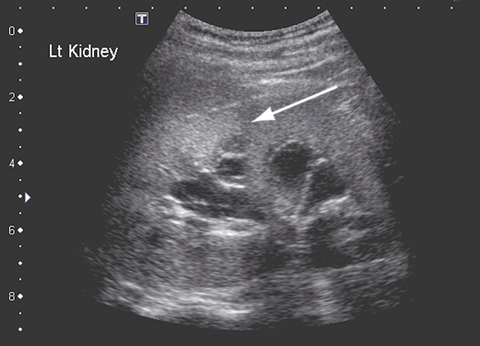

After 5 weeks of treatment with amphotericin B, the patient became unwell, with a high fever and moderate renal impairment. His creatinine level had increased from 0.06 to 0.17 mmol/L (RR, 0.03–0.08 mmol/L); his urea level was 18.7 mmol/L (RR, 2.1–6.5 mmol/L), and the glomerular filtration rate was 29 mL/min (RR, 100–140 mL/min). A renal ultrasound scan revealed parenchymal fungal spores (Figure B). Amphotericin B treatment was ceased and twice daily oral posaconazole 400 mg commenced. Renal function normalised within about 7 days. Follow-up imaging 6 weeks later revealed resolution of renal fungal disease.

B: Renal fungal spores (arrow).